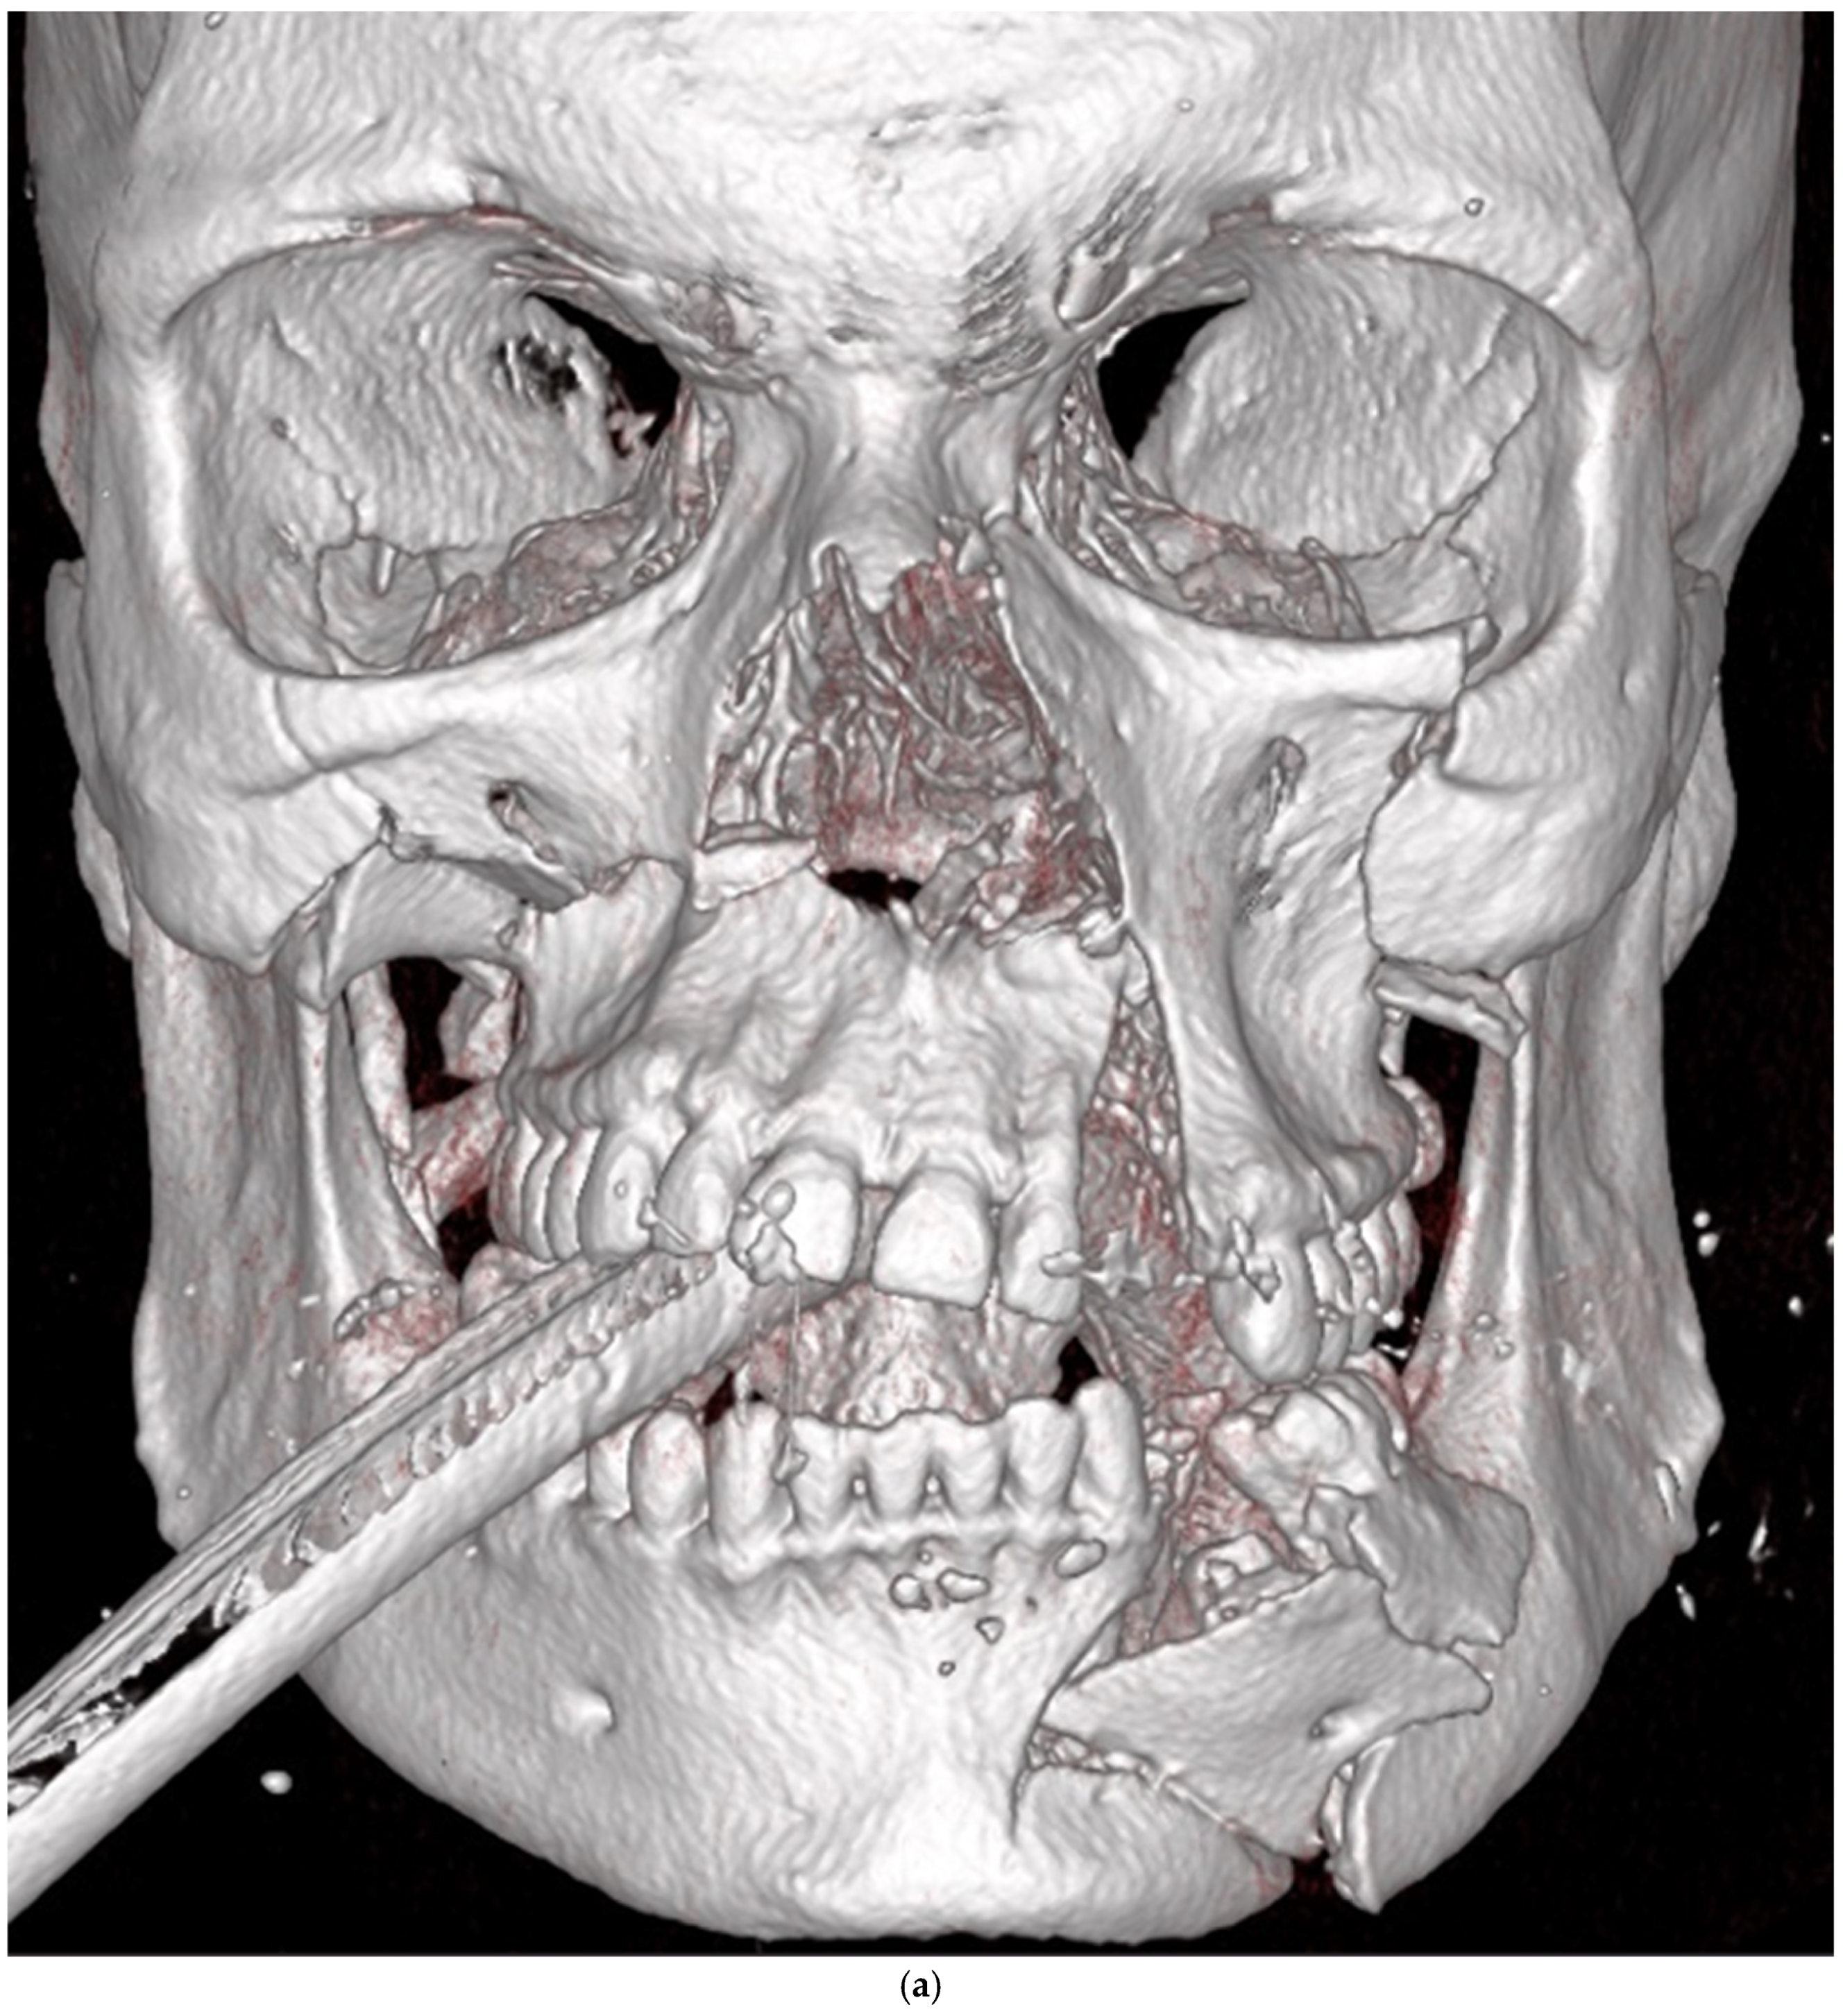

| Midface | 13 | ||||

| Zygomatico–orbital complex * | 6 | 4 | 6 inadequate reductions | ||

| Le Fort ** | 4 | 1 (Le Fort III) | 4 inadequate reductions | ||

| Orbit | 4 | 0 | 3 inadequate reconstructions of orbital floor fractures, 1 orbital deformity due to inadequate reduction of the zygomatic bone | ||